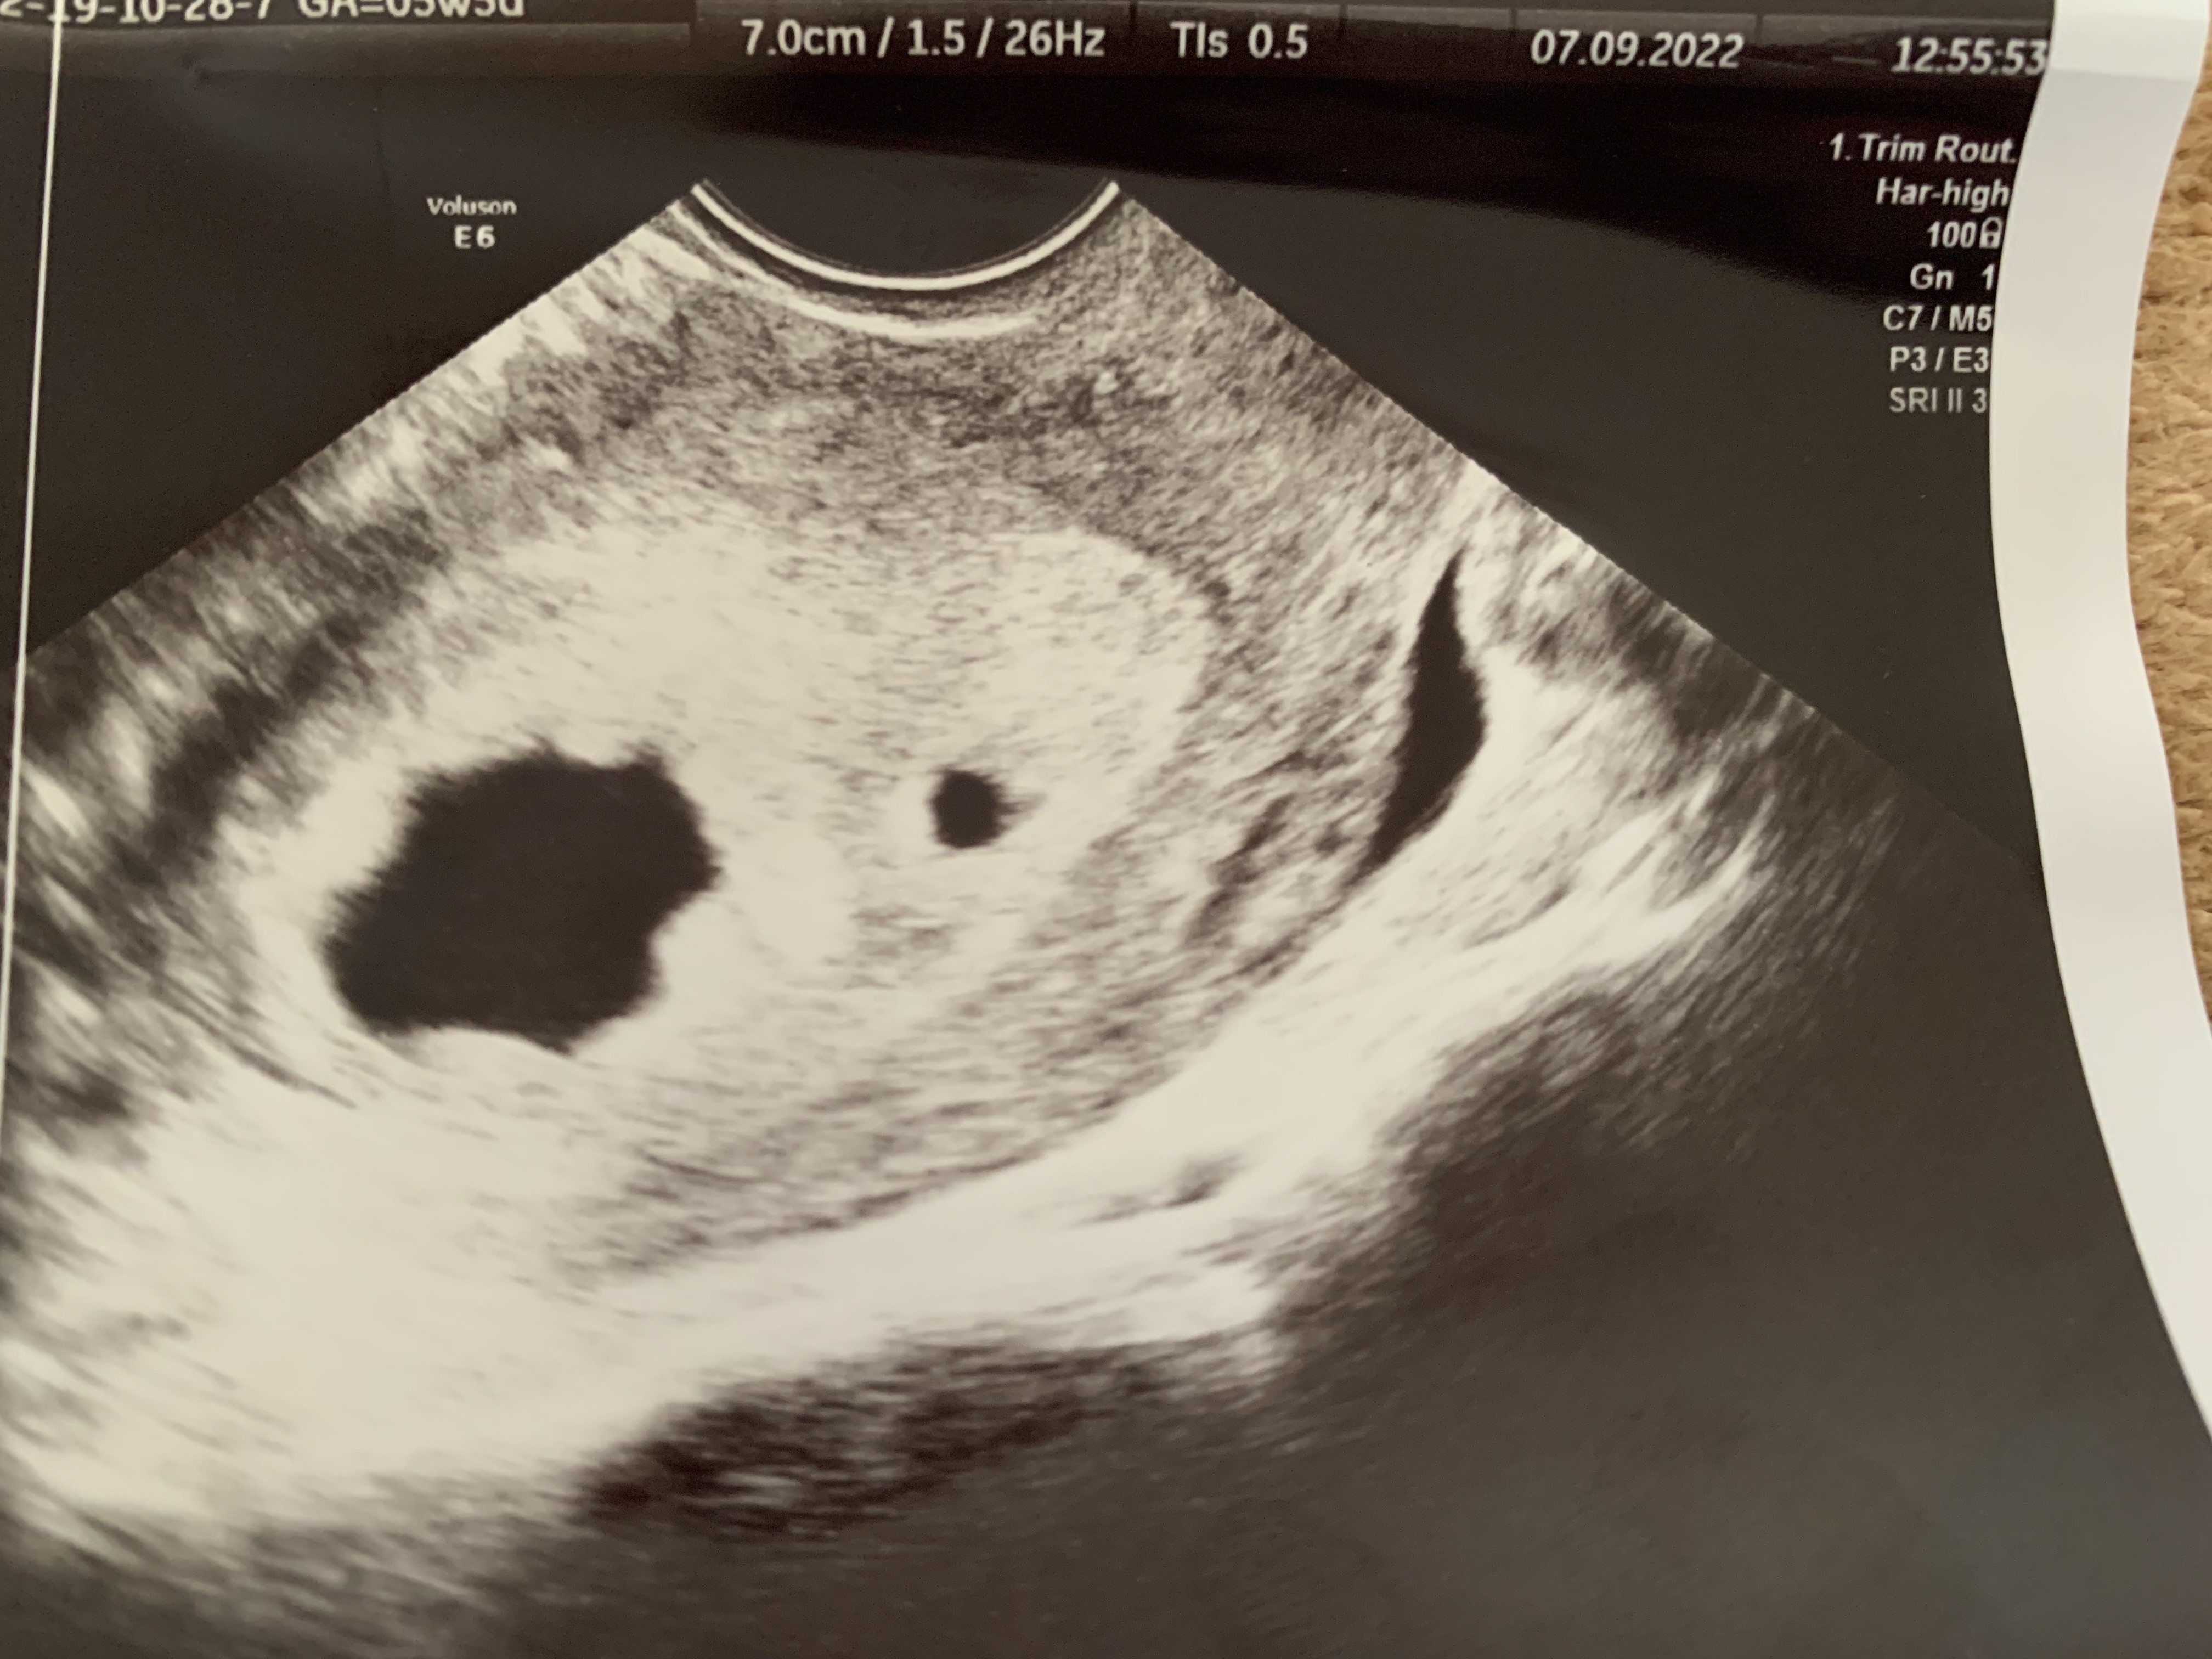

Myślę że nie ma co porównywać bo wszystko zależy od owulacji i zagnieżdżenia. Ja np miałam owu najprawdopodobniej w 14-15dc i wczesne zagnieżdżenie wiec w 6+0 już biło serduszko ale wystarczy że miałaś owu 4 dni później i zarodek jeszcze się nie pokazał i ma do tego prawoTak czytam wasze wpisy i to jakie macie wyniki na usg i zastanawiam się. Pęcherzyk ciążowy miałam 15mm a pęcherzyk zoltkowy 3,7mm w 5t6d. Czy jednak powinnam się martwić ze nie było zarodka? :/ poza tym jak teraz zaczęłam oglądać usg to zauważyłam jakby drugi pęcherzyk. Wrzucę zdj, proszę oceńcie to swoim wprawionym okiem